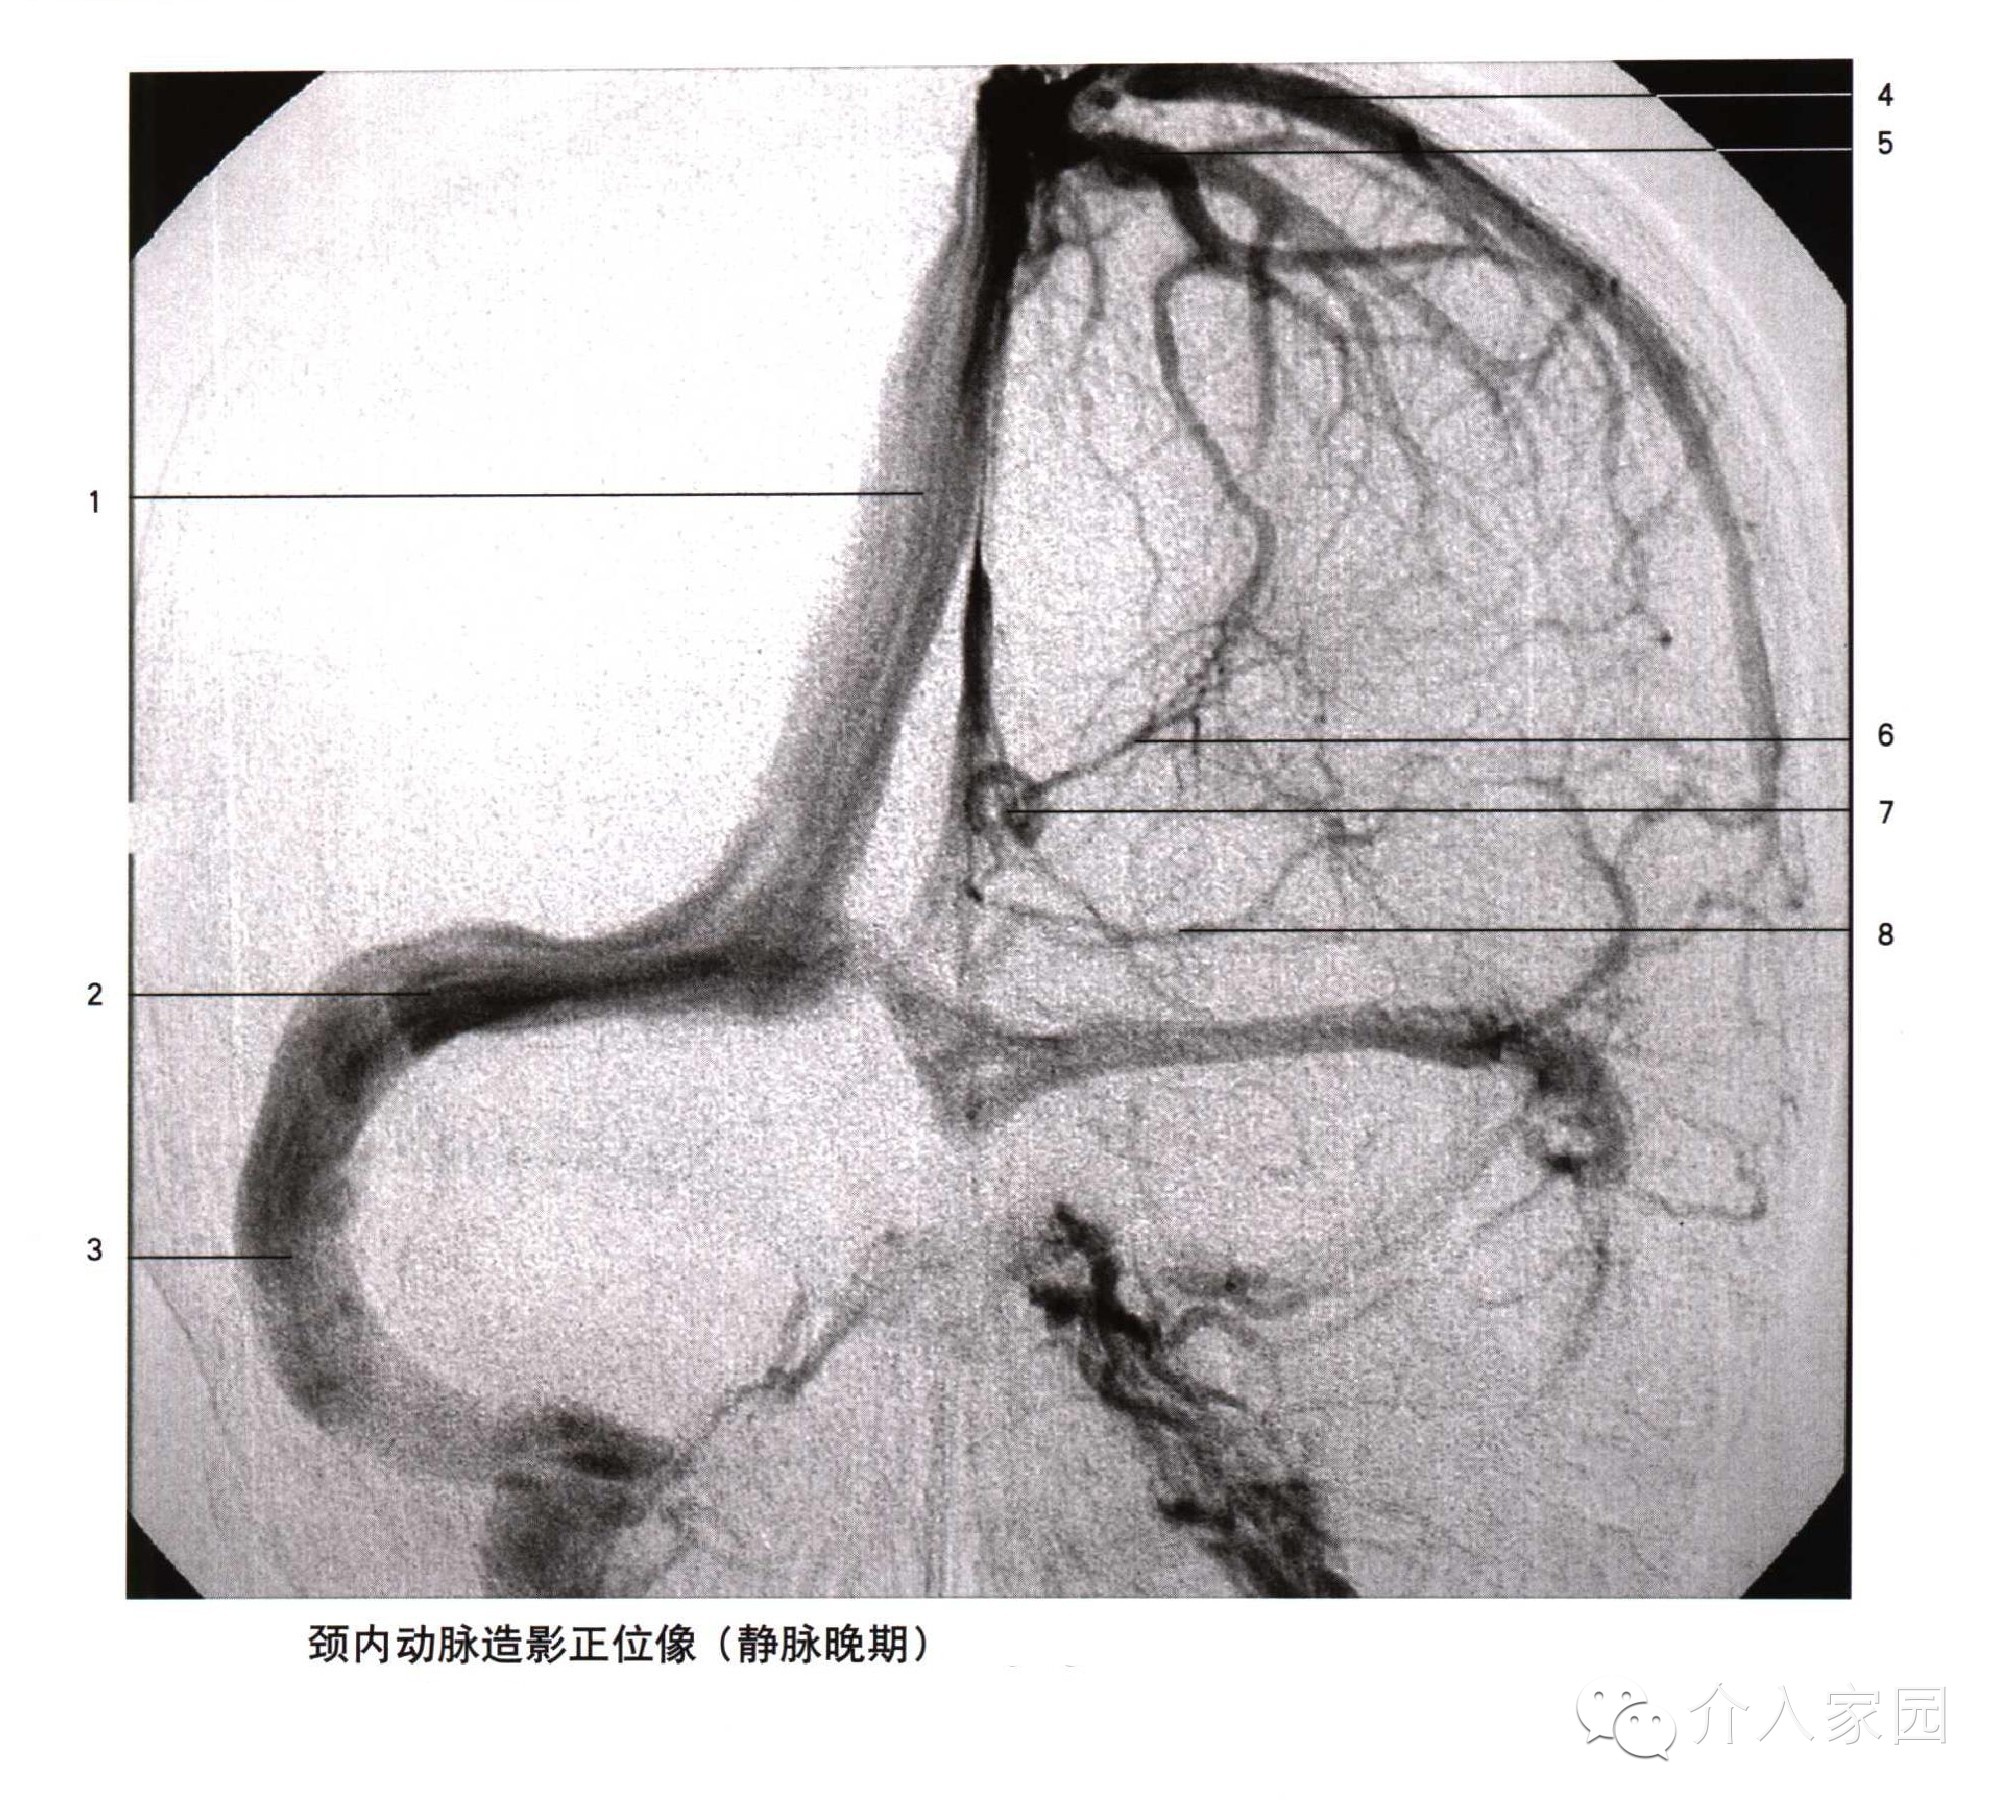

1、上吻合靜脈 2、額升靜脈 3、大腦中淺靜脈 4、海綿竇 5、岩上竇

6、岩下竇 7、中央溝靜脈 8、頂枕升靜脈 9、顳後靜脈 10、下吻合靜脈

1、上矢狀竇 2、橫竇 3、乙狀竇 4、中央溝靜脈

5、上吻合靜脈 6、丘紋靜脈 7、靜脈角 8、基底靜脈